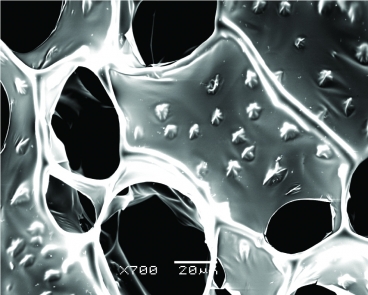

纳米线 - 海藻酸钠复合支架电镜扫描图像。

论文中介绍,在工程心脏组织中添加金线能增强其导电性,是对现有纳米补丁的改良。这种金纳米线平均30纳米粗,2微米至3微米长,肉眼几乎无法看到。经过培养之后,布满金线的补丁上的心肌细胞变得更厚,排列得也更有组织。用电流刺激细胞,会产生一个明显的电压峰值,相邻的心肌细胞束之间的电流活动明显提高。与之对比,没有金纳米线的补丁仅能产生微弱电流,使一束细胞跳动。

Nanowired three-dimensional cardiac patches